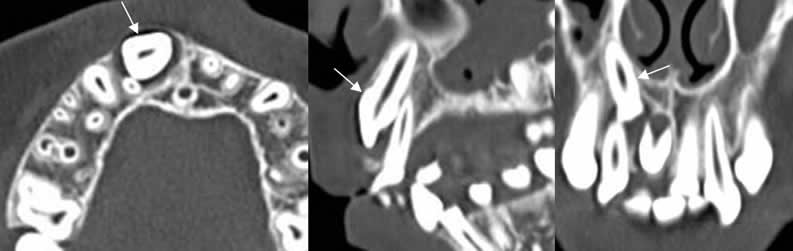

Fig 83. Mesiodens.

A: TAC axial, B: TAC reconstrucción sagital y C: TAC reconstrucción coronal. Diente supernumerario incluido, por mesiodens.